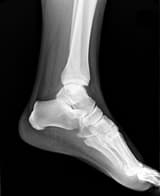

S., a young professional with a chronic non-healing stress fracture, arrives in a state of frustration and hopelessness. What follows is an amazing journey of self-healing and self-discovery, of doubts and frustrations, culminating in a whole new perspective towards body and life. The healing journey is recounted directly by the patient, retaining the authenticity of personal experience. This case holds a special significance for the therapist; for herein he first saw the power of love to heal his body. The case revealed many other intriguing mysteries of the body and its healing process, many of which may have universal implications. The consciousness approach is much more than a mere healing of the body or even the mind; it has the power to evoke change at a much more fundamental level of our being.